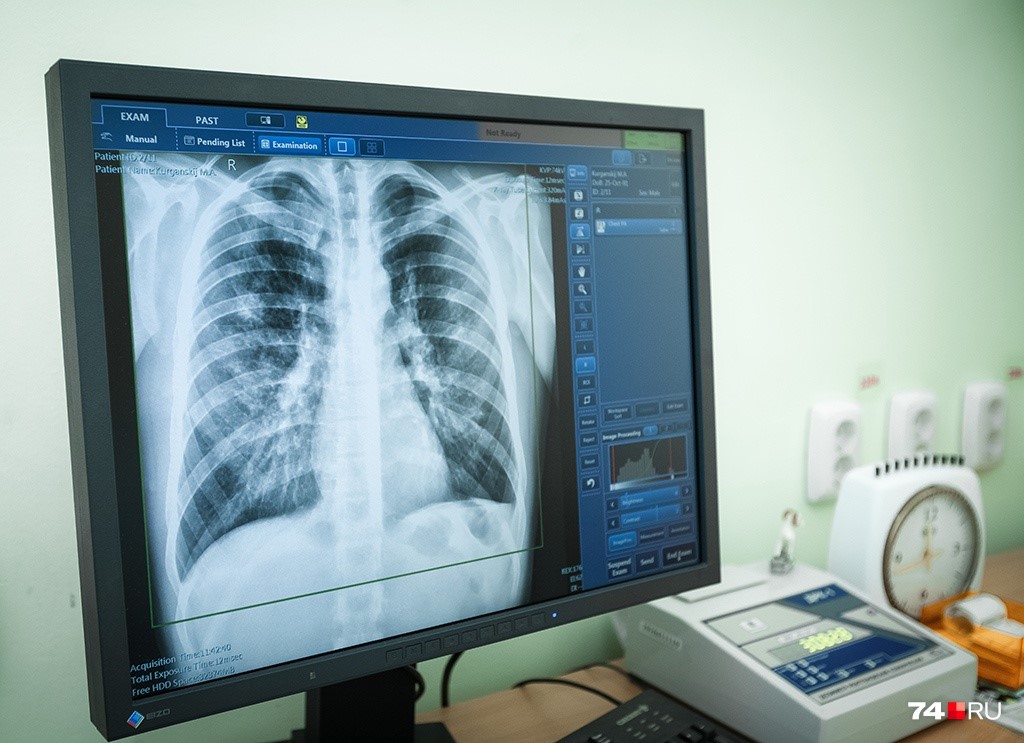

Наши коллеги открыли двери филиалов для всех граждан: в часы работы любой человек, независимо от места жительства мог сделать флюорографию, проконсультироваться с врачом-фтизиатром. Листовки, плакаты и рукотворные санитарные бюллетени размещались не только в стенах филиалов, но и в людных местах населенных пунктов. Статьи в газетах, сюжеты на телевидении, лектории в образовательных учреждениях – это все тоже было. Не забыли и про своих коллег, работающих в учреждениях здравоохранения общего профиля – проводили лекции, напоминали о том, что настороженность медицинских работников в отношении туберкулеза нельзя снижать, необходимо расширять круг пациентов, которых в обязательном порядке, в рамках диспансеризации или обычного визита к врачу, направлять на флюорографическое обследование.